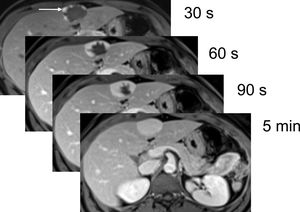

The morphology of contrast uptake during the dynamic sequence (biodistribution) is crucial for lesion characterisation, for example in liver tumours. Although there is overlap between the different lesions and their behaviour in dynamic studies, in most cases it provides information that aids in lesion characterisation. For example, a liver tumour with nodular and peripheral contrast uptake in the early phases, which progresses towards the centre of the lesion and is hyperintense with respect to the surrounding liver in the last phase of the dynamic sequence is typically a haemangioma (Fig. 4). Hepatic hypervascular lesions show intense uptake in the arterial phase, with contrast washout in the other phases of the dynamic sequence. This contrast biodistribution can be identified in focal nodular hyperplasia (Fig. 5), certain subtypes of adenoma, in hepatocellular nodules in the cirrhotic liver, and in hypervascular metastases.

Dynamic multiphase T1-weighted gradient echo sequence with spectral fat suppression after GBCA administration. Hepatic haemangioma with nodular and peripheral contrast uptake in the initial phases of the dynamic study (white arrow), progressing towards the centre during the sequence. In the last phase, it is completely filled with contrast, being hyperintense with respect to the adjacent liver parenchyma.